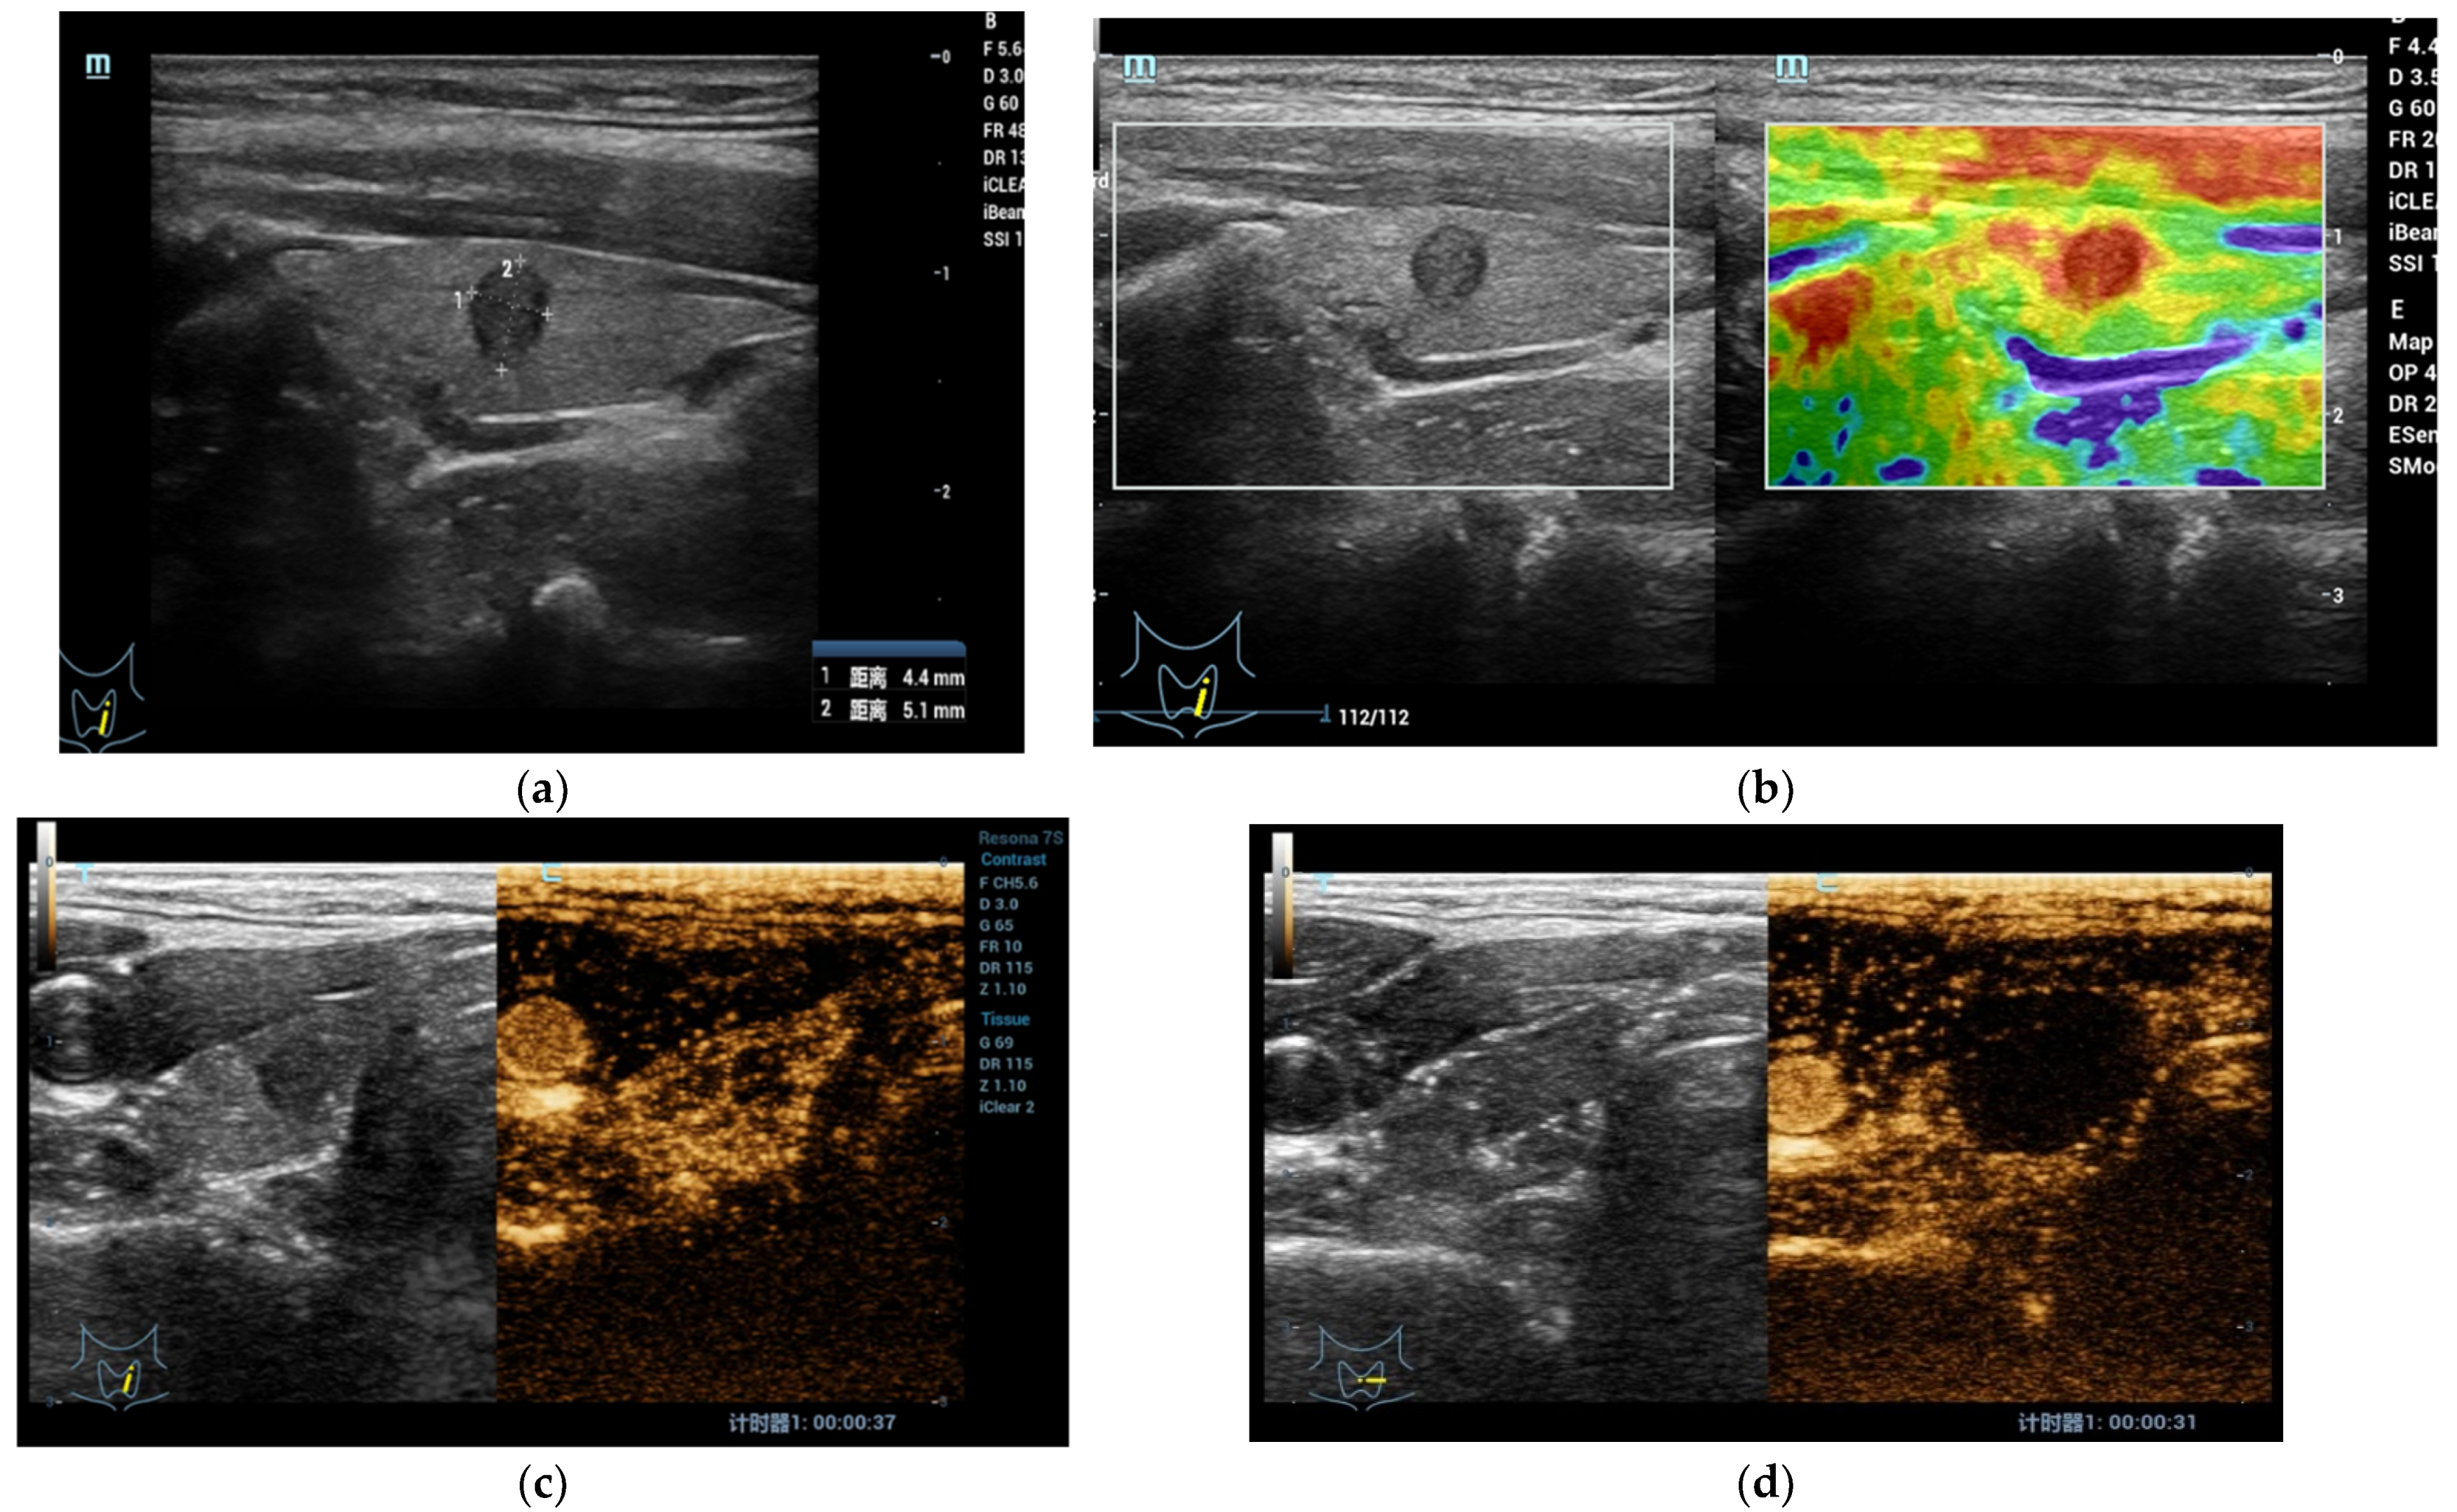

3.3. Evaluation of Lymph-Node Local Staging Using CEUS

- Xiang, D.; Hong, Y.; Zhang, B.; Huang, P.; Li, G.; Wang, P.; Li, Z. Contrast-enhanced ultrasound (CEUS) facilitated US in detecting lateral neck lymph node metastasis of thyroid cancer patients: Diagnosis value and enhancement patterns of malignant lymph nodes. Eur. Radiol. 2014, 24, 2513–2519. [Google Scholar] [CrossRef]

- Zhan, J.; Diao, X.H.; Chen, Y.; Wang, W.P.; Ding, H. Homogeneity Parameter in Contrast-Enhanced Ultrasound Imaging Improves the Classification of Abnormal Cervical Lymph Node after Thyroidectomy in Patients with Papillary Thyroid Carcinoma. Biomed Res. Int. 2019, 2019, 9296010. [Google Scholar] [CrossRef]

- Hong, Y.R.; Luo, Z.Y.; Mo, G.Q.; Wang, P.; Ye, Q.; Huang, P.T. Role of Contrast-Enhanced Ultrasound in the Pre-operative Diagnosis of Cervical Lymph Node Metastasis in Patients with Papillary Thyroid Carcinoma. Ultrasound Med. Biol. 2017, 43, 2567–2575. [Google Scholar] [CrossRef]

- Chen, L.; Chen, L.; Liu, J.; Wang, B.; Zhang, H. Value of Qualitative and Quantitative Contrast-Enhanced Ultrasound Analysis in Preoperative Diagnosis of Cervical Lymph Node Metastasis from Papillary Thyroid Carcinoma. J. Ultrasound Med. 2020, 39, 73–81. [Google Scholar] [CrossRef]